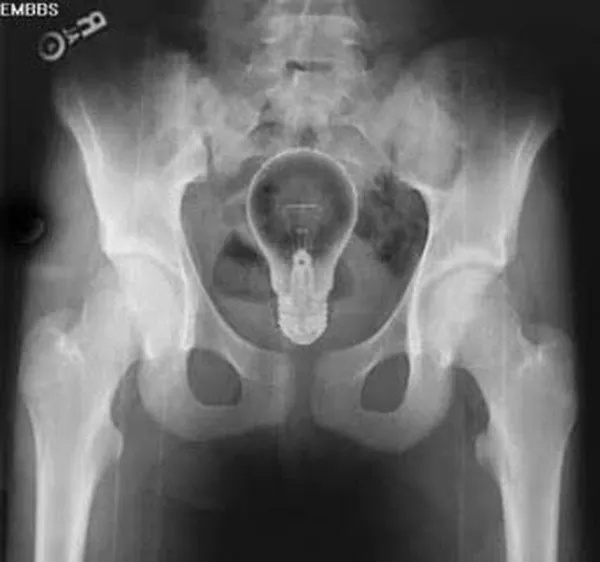

I can’t fathom how the light inside your body cure has gone out of fashion.